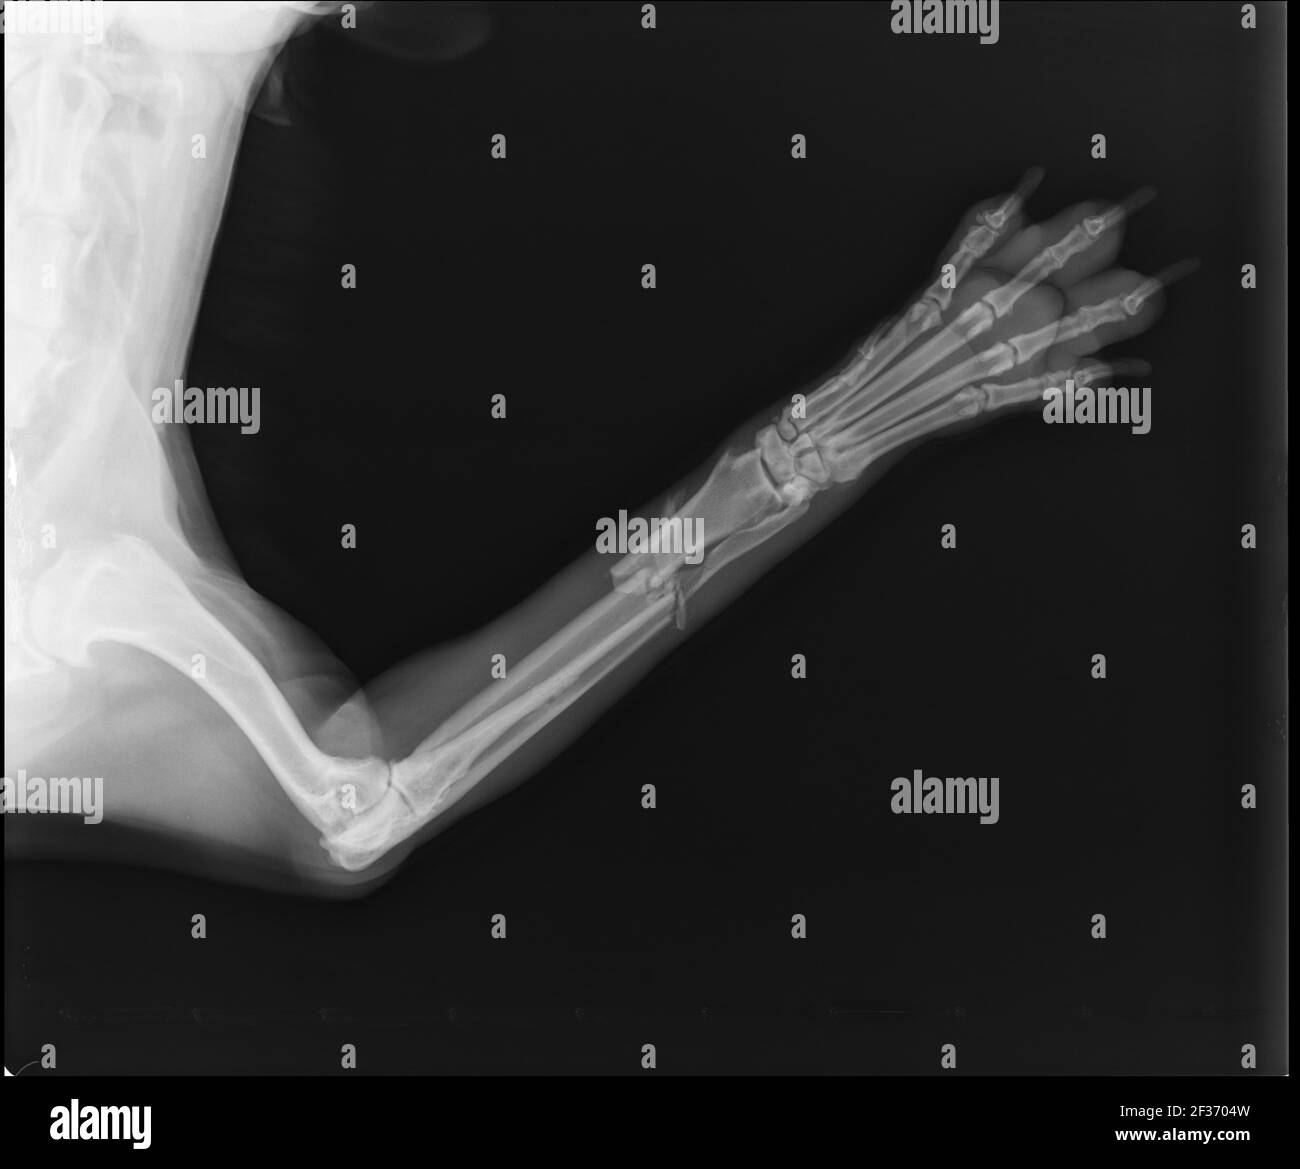

Dog x ray radius and ulna fracture. Canine broken leg StockFoto

From www.alamy.com

Dog X Ray Showing Radius and Ulna Fracture. Cranial View Stock Photo Radius Vs Ulna Dog It is not uncommon for a dog or cat to fracture its forearm. The two bones that are usually involved are the radius and ulna. Radius and ulna fractures are common in small breed dogs, where they frequently affect the distal diaphysis. Assessment of fracture healing after minimally invasive plate osteosynthesis or open reduction and internal fixation of coexisting radius. Radius Vs Ulna Dog.